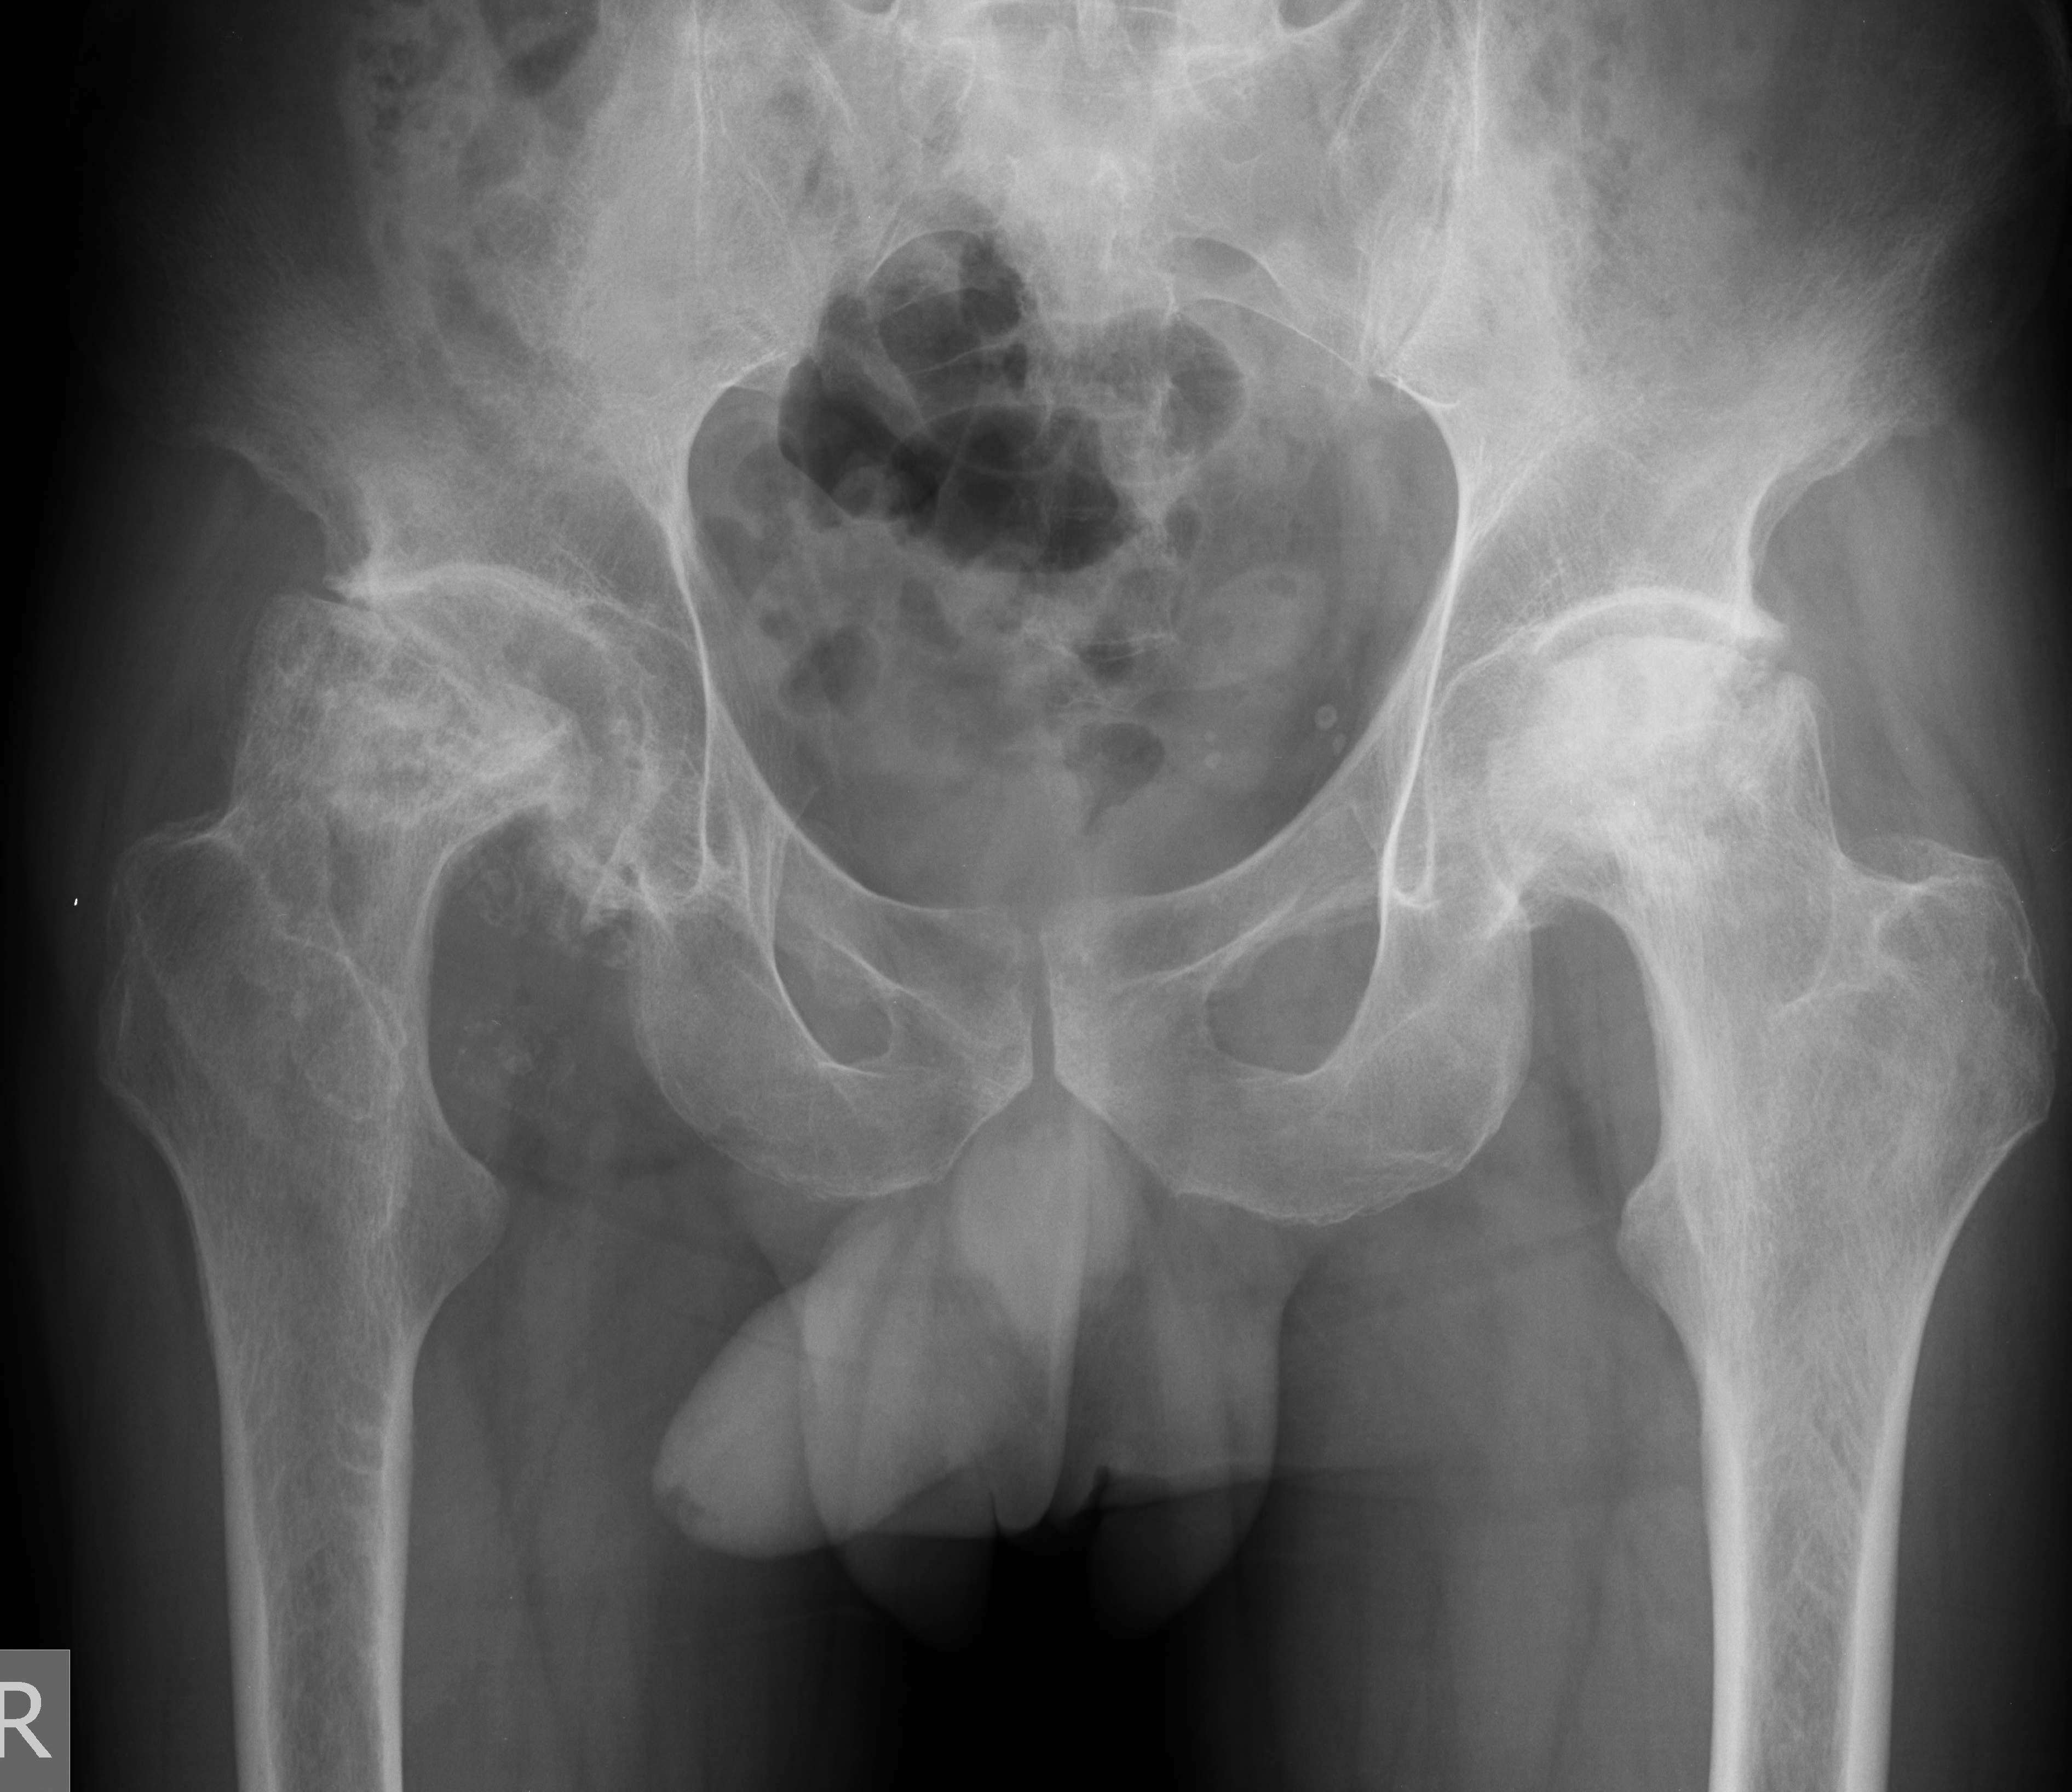

- Ендопротезиране на колянна и тазобедрена става

Основно лекувам заболявания на тазобедрена и колянна става чрез минимално инвазивно ендопротезиране, следтравматични и дегенеративни нарушения на ръката и китката и халукс валгус (популярен като „кокалчета на краката”).